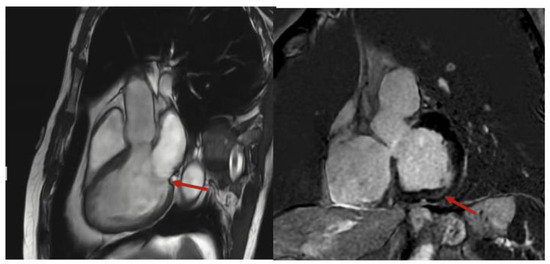

2. Case Presentation